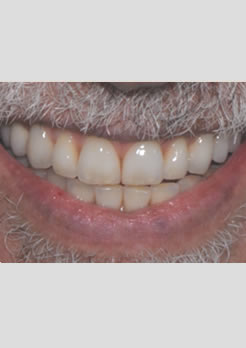

Instalação das próteses com uma nova dimensão vertical de oclusão e novo posicionamento dos lábios e musculatura facial